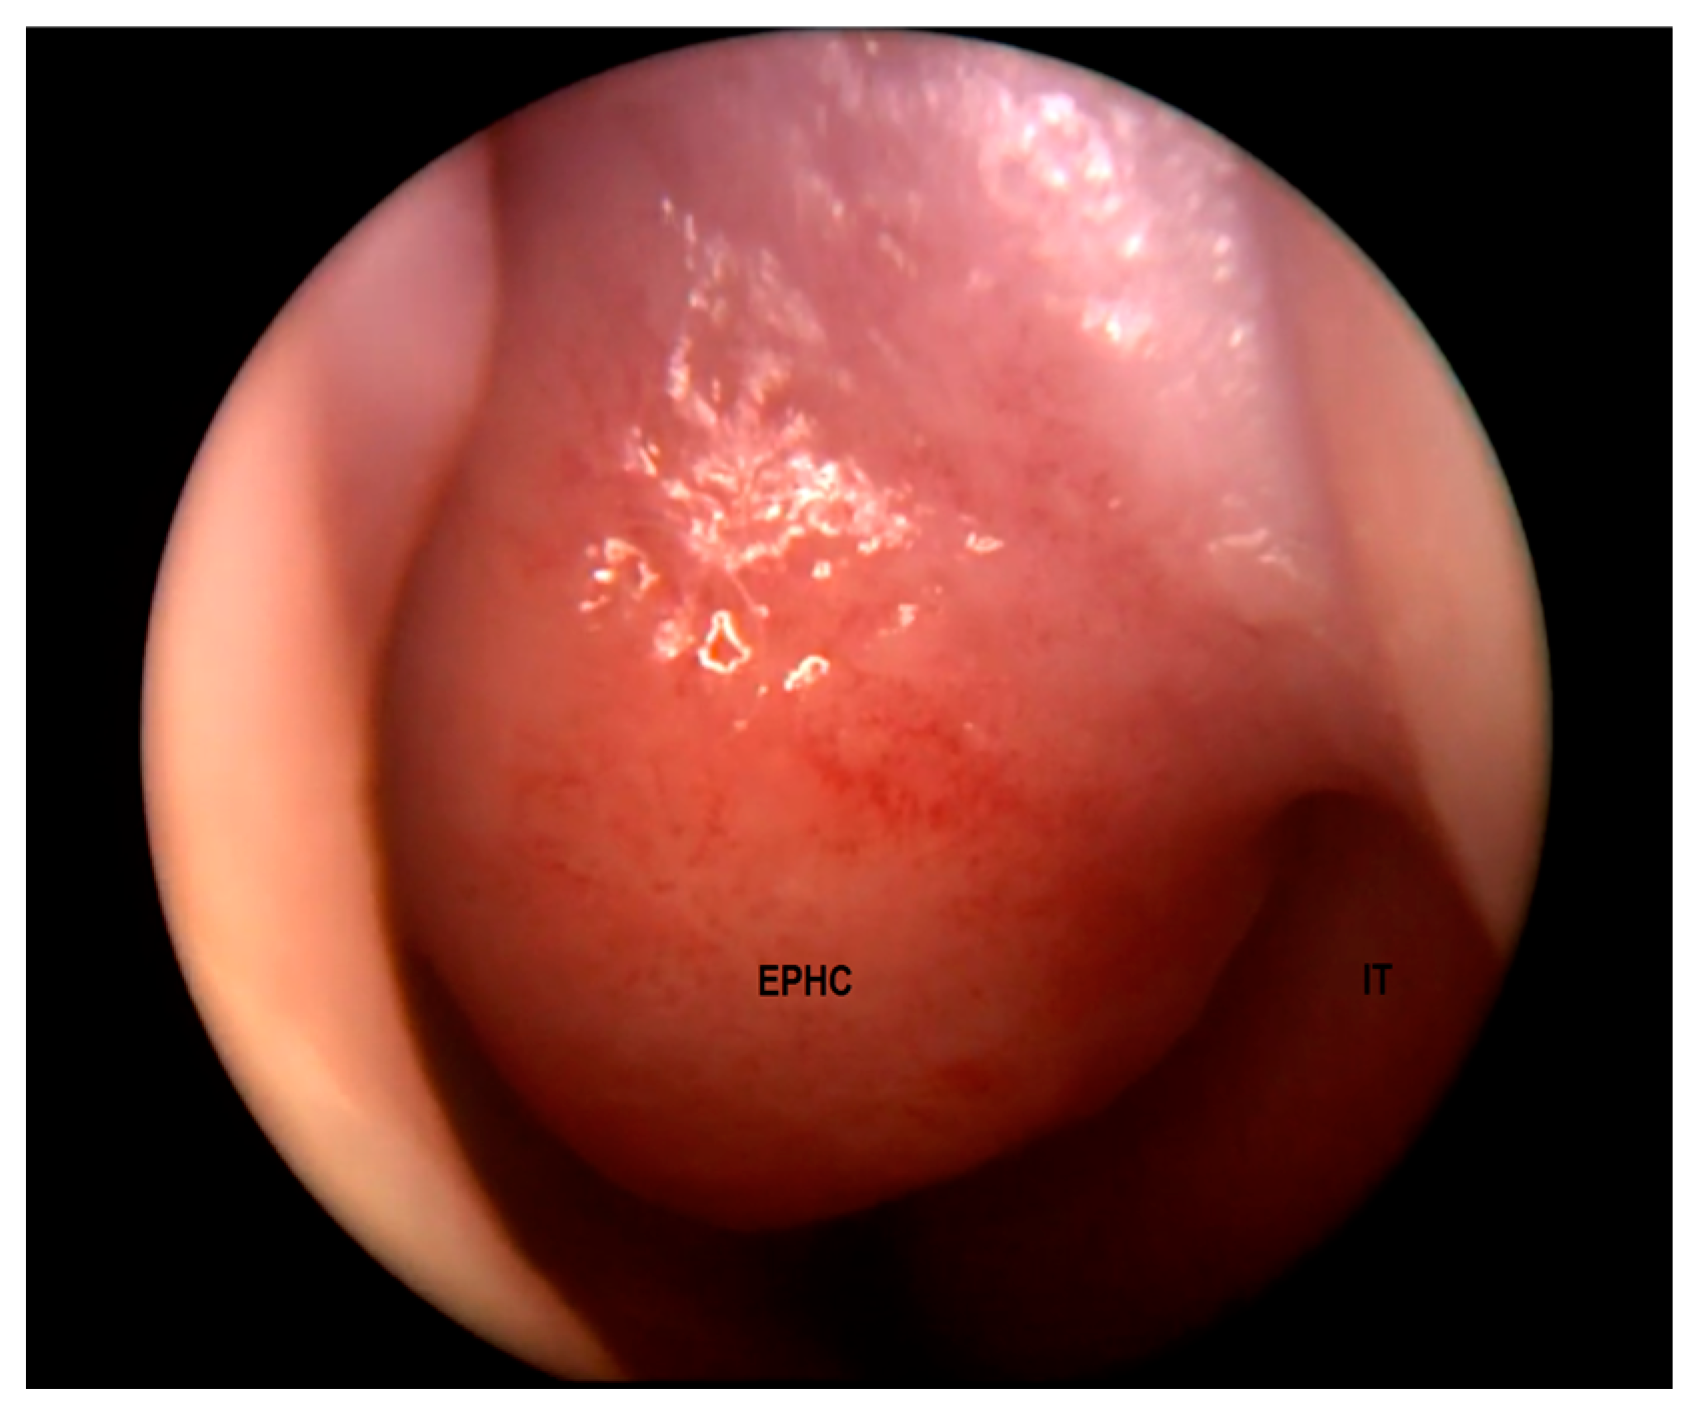

| Characteristics | Hair visible in the skin ostium; non-expansile, non-pulsatile, non-compressible, and non-transilluminating mass | Tends to grow along with the patient; firm and non-compressible mass, non-transilluminating; intranasal—pale, “polypoid”; extranasal—smooth, well-circumscribed, reddish or bluish, often with telangiectasis on its surface | Smooth “polypoid” mass, pink or bluish, covered with mucous membrane, usually pulsatile, transilluminating, soft, and compressible | |

| MRI | Variable signal intensity depending on the protein content; fat-suppressed T1-weighted images—differentiation between skull base defects and enhancing non-ossified cartilage of anterior cranial fossa; DWI—typically high-signal-intensity lesion with corresponding low signal intensity on ADC maps | Discontinuity with the brain parenchyma; variable visualization of a fibrous stalk connection to CNS; well-circumscribed, rounded, or polypoid mass—isointense or rarely hypointense to gray matter on T1-weighted imaging; neural tissue—more hyperintense on T2-weighted images to normal brain parenchyma in most cases; dysplastic tissue usually corresponds with no enhancement or moderate enhancement; noticeable enhancement at the lesion periphery | Herniation of intracranial tissue and its continuity with the brain | |